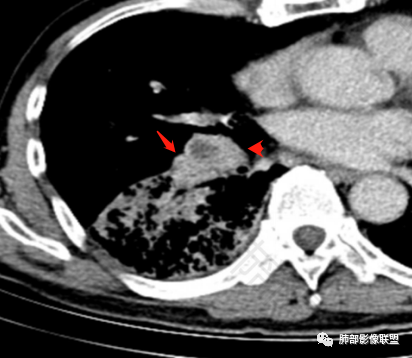

双肺慢支肺气肿。右肺下叶大片状影,支气管狭窄,枯枝状。间杂网格状影,实变影(与胸膜糊墙),叶间裂膨隆。右肺门增大。增强后右下肺片状影内血管束失去正常形态,边缘模糊。实变影不均匀强化。纵隔及右肺门多组淋巴结肿大,其中右侧10、11、12组淋巴结肿大内见液化。考虑肺炎型肺癌并感染?不典型结核待除外。左下小片影?(层面不全)。

右肺下叶大团块影,斜裂膨隆,内支气管破坏,纵隔窗实质性成份少有强化(假大空),肿瘤CA125、199高,考虑粘液腺Ca右肺门淋巴结及纵隔淋巴结大,右肺下动干起始处充盈缺损(示栓塞或Ca栓;余肺叶弥散网格状改变,间质增厚及纤维化表现!

老年男性的病人。慢性的咳嗽憋喘为主的症状,慢性的病程。临床ca199明显的增高,癌胚抗原升高。白细胞增高提示有肺部感染的。影像学表现两肺弥漫性的网格状改变。而病变又集中在右肺下叶。右肺门见一个大结节的病灶,内部有片状坏死,不均匀的强化,邻近的支气管变窄,周围的肺组织呈大片状的实变影。纵隔淋巴结多个肿大。这样的影像学考虑右侧肺门旁的恶性病变。鳞癌或者粘液性腺癌,伴纵隔淋巴结转移,右肺下叶的癌性淋巴管炎,两肺慢性的间质性肺炎。

老年男性,反复咳嗽咳痰喘憋8年,加重10天,发热半天。白细胞计数明显升高(存在细菌感染可能),CEA、CA19—9升高(肺癌或间质性肺疾病引起可能)。痰培养见肺克。CT;双肺弥漫小叶间质、中轴间质增厚,胸膜下肺气肿,右肺门及右下叶可见实变影,边界模糊,内支气管走形僵硬,部分见蜂窝样改变,增强后实变区可见低密度区(粘液?),叶间裂膨隆,纵隔及右肺门见肿大淋巴结,右肺门淋巴结内见坏死。存在感染,但单纯感染难以解释支气管走行僵硬、实变内的低密度病灶,考虑恶性伴感染,肺炎性肺癌或黏液腺癌。

2.影像表现:肺气肿背景,右肺下叶呈现明显网格影及蜂窝影、枯枝征,边缘膨隆、叶间裂向前方推移。病灶密度不均,前份见不规则片状实性密度区,实性部分轻度强化,边界不清,周边特征掩盖不清。支气管主要分支显示,呈枯枝征。纵隔窗病灶密度偏低,病灶内血管影边缘稍显模糊,未见明显液化坏死区。

右侧肺门淋巴结肿大,中央低密度;纵隔见轻度增大淋巴结。